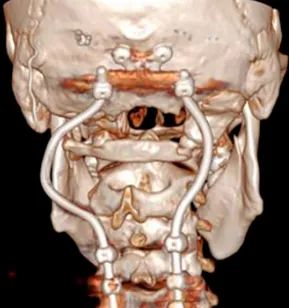

针对颅颈不稳定的问题,手术团队在颈椎的C0、C3、C4及C5椎体上精准置入根钉。这些根钉经过特殊设计,采用曲线方式横向弯曲,使其完美贴合颈椎的生理曲度。此种固定方式在提升稳定性的同时,有效减少了对周围软组织的潜在损伤。根钉植入后,采用Roy-Camille技术完成枕颈融合(C0-C3-C4-C5)。融合过程中,使用生物材料填充椎体间空隙,以促进骨组织生长与愈合,最终增强颈椎的整体稳定性。

需要特别指出的是,固定根钉的曲线形横向弯曲设计,核心目的之一是为患者后续的质子治疗创造出一个无金属干扰的定位与治疗通道。术后CT与MRI复查证实肿瘤已达完全切除,病理学检查确认为典型脊索瘤。术后患者吞咽功能显著改善,颈部疼痛缓解。在恢复数周后,该患者顺利接受了质子治疗。